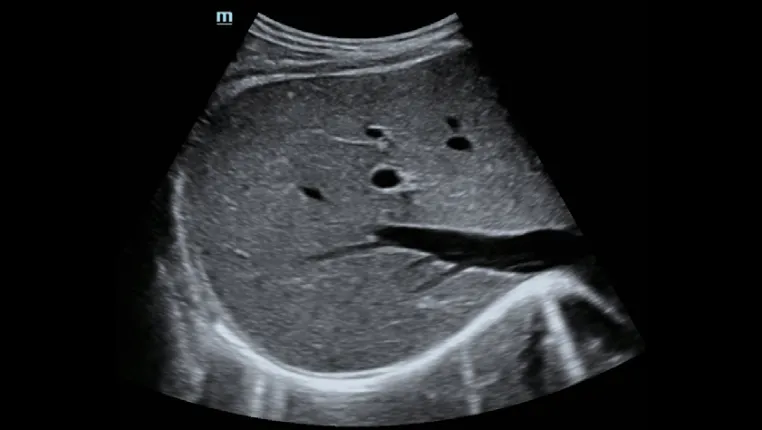

- Специальная пункция под ультразвуковым контролем для повышения точности биопсии

Пункция печени под контролем ультразвука